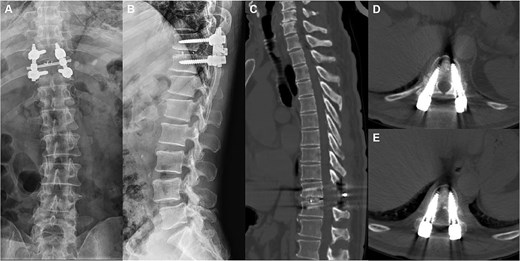

A 66-year-old male presented with a 1-year history of progressive low back pain and bilateral lower limb numbness, intensifying over the preceding month. Symptoms began insidiously without trauma and progressively worsened with prolonged standing and walking, improving with rest. The patient described deep, aching pain that significantly impacted his daily activities. Physical examination revealed bilateral lower limb numbness, especially prominent in the anterior thighs, an unsteady gait with a broad-based stance, decreased quadriceps muscle strength, reduced sensation below the navel extending to the groin, and positive bilateral Babinski signs indicating upper motor neuron involvement. Initial external X-rays suggested only L4 vertebral displacement, inconsistent with the clinical findings, prompting hospital admission for further evaluation. Refined imaging studies revealed previously unrecognized pathology. X-ray (Fig. 1A) and CT (Fig. 1B–D) demonstrated concomitant T10 vertebral body slippage, while MRI (Fig. 1E) showed severe T10/11 spinal cord compression with associated signal changes. The patient was diagnosed with thoracic spinal stenosis due to T10–T11 vertebral slip, explaining the bilateral lower extremity neurological symptoms and gait instability. Given the prolonged symptom duration, recurrent nature, and functional impact, surgical intervention was indicated after multidisciplinary discussion. The patient underwent T10–T11 thoracic interbody fusion with comprehensive decompression under general anesthesia. The procedure included herniated disc material removal, extensive posterior decompression, precise pedicle screw and titanium rod placement for stabilization, and autologous iliac crest bone grafting for interbody fusion. Postoperative management included comprehensive pain control and neurological monitoring. Follow-up X-ray (Fig. 2A and B) and CT (Fig. 2C–E) demonstrated successful vertebral realignment with the internal fixation in the ideal position. By postoperative Day 6, the patient reported significant back pain and leg numbness relief. Progressive improvement with structured physical therapy led to discharge on Day 10. One-year follow-up examination (Fig. 3) revealed stable fixation with continued symptom resolution, enabling free ambulation and complete return to normal activities.

The preoperation imaging examinations. A sagittal X-ray (A) shows concomitant anterior displacement and instability of T10 and L4. A sagittal CT image (B) similarly demonstrates vertebral body slippage at T10, with stenosis and disc herniation of the spinal canal at the corresponding segments (C, D). T2-weighted imaging MRI (E) demonstrates severe spinal cord compression, with neurologic ischemic degeneration.